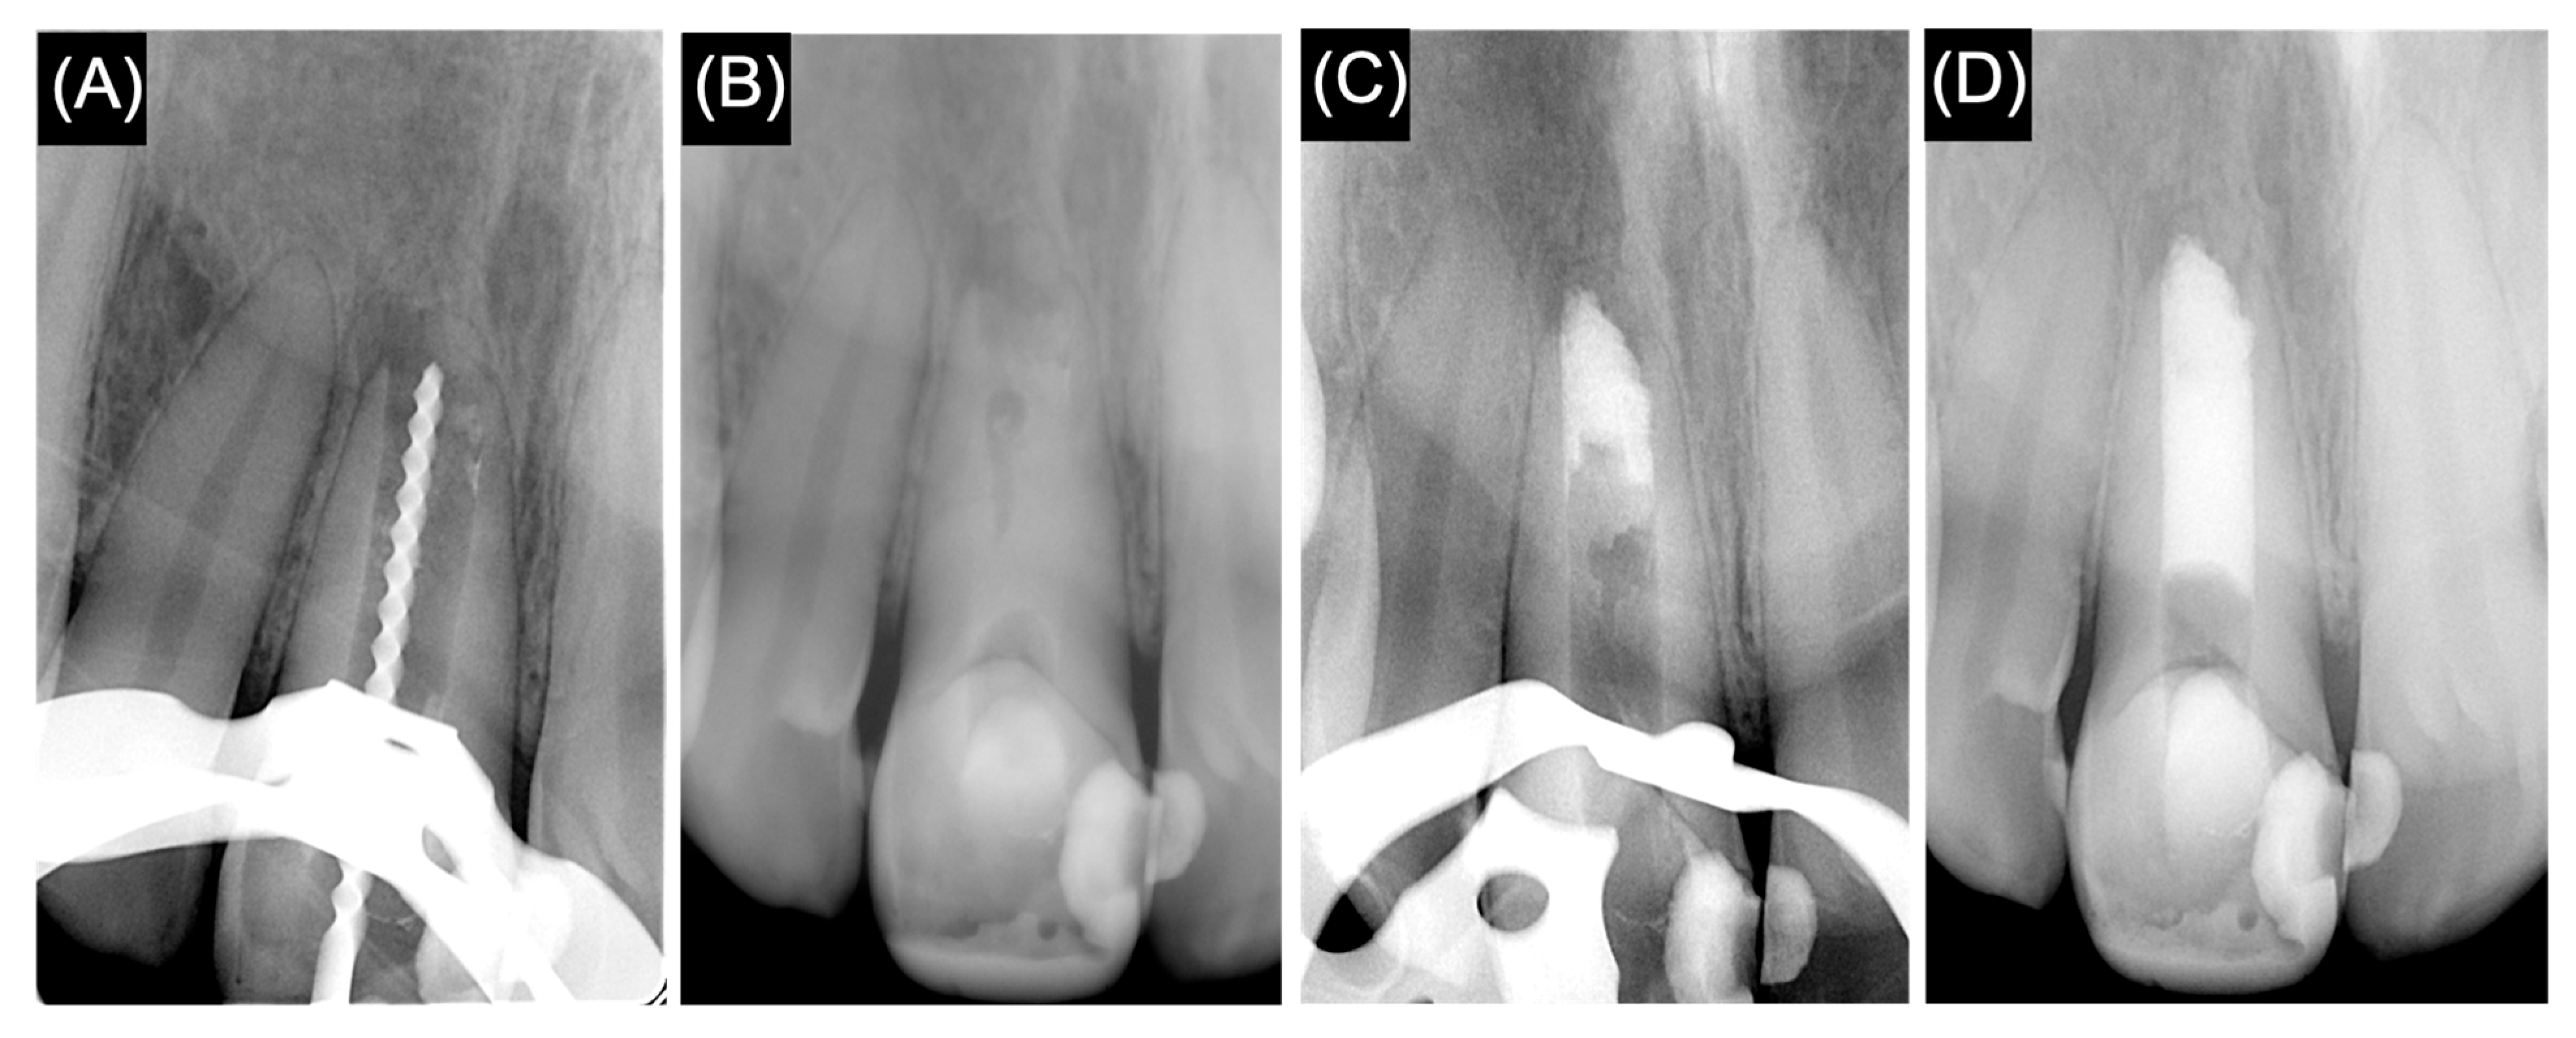

2. Case Presentation

2.1. First Treatment Visit

2.2. Second Treatment Visit

2.3. Follow-Up Visit